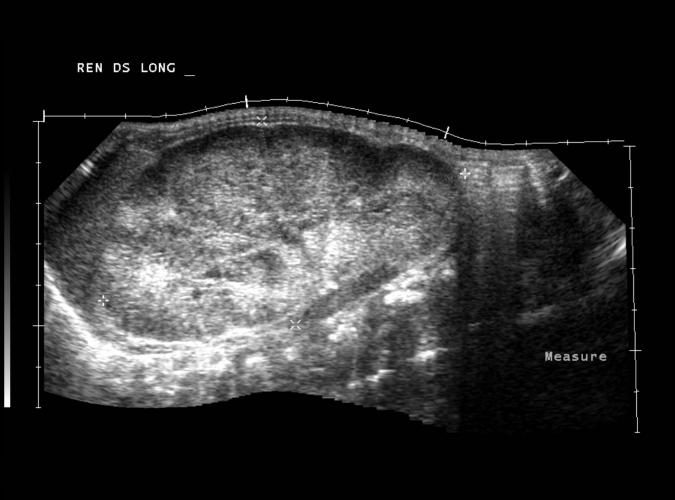

av Catherine Olsson, sonograf

Long. Höger njure

Nyfödd med bilateral polycystiska njure,10cm lång.

...se bild 9f.